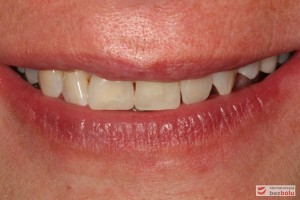

Do naszej placówki zgłosiła się starannie planująca swoje działania Europejka, mieszkająca na stałe w Kotlinie Jeleniogórskiej. Jej oczekiwania dotyczyły bardzo metodycznie zaplanowanego planu leczenia. Celem jaki postawiła przed naszym zespołem lekarzy było wyeliminowanie wszystkich wątpliwych i nierokujących wypełnień, a także poprawa estetyki w zakresie lewego siekacza centralnego w szczęce. Został rozpisany blisko dwuletni plan wymiany zużytych i nieszczelnych wypełnień amalgamatowych i kompozytowych. Zaplanowano również przygotowanie endodontyczne wybranych zębów w szczęce i żuchwie, a także zaopatrzenie w inlay’e porcelanowe i korony ceramiczne wykonane w systemie e-max.